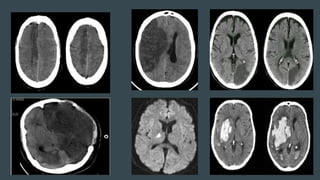

Types of Stroke

Subdural

hemorrhage

Ischemic

infarction

Intracerebral

Subarachnoid